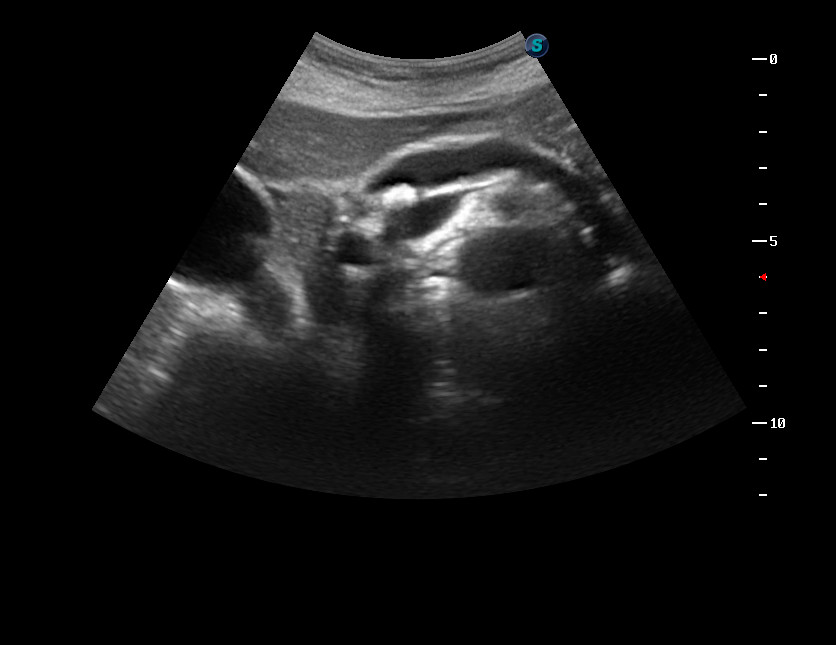

УЗИ, камень в пузырном протоке

Женщина средних лет с жалобами на боли в эпигастральной области. От болей не спала всю ночь.

Что такое может б\ыть?